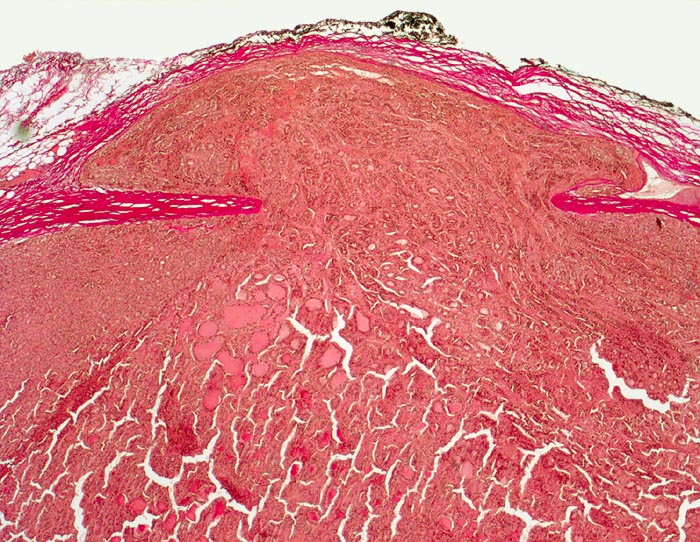

PathoPic – image database / PathoPic ID 4951 - Follikuläres Schilddrüsenkarzinom: Kapseldurchbruch

Follikuläres Schilddrüsenkarzinom: Kapseldurchbruch

Follikulärer Tumor mit dicker Kapsel. Der Tumorknoten ist zwar von einer Neokapsel bedeckt, hat aber eine imaginäre Linie entlang der ursprünglichen Kapsel überschritten.

Vor einem Jahr Schilddrüsenteilresektion wegen follikulärem Karzinom. Jetzt Resthyreoidektomie wegen Rezidiv.